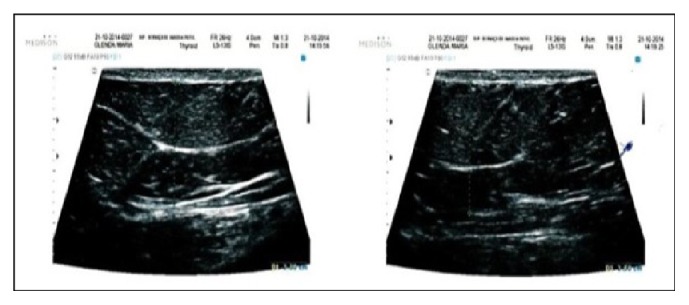

The qualitative analysis performed by the sonographer is demonstrated in Figures 3, 4, 5, 6, and 7.

Figure 3.

Sonography before treatment.

Figure 4.

Sonography, 7 days after treatment.

The results obtained with the ultrasound demonstrate a decreasing in the fat layer thickness averaged 1.46 cm after the treatment. It was also possible to verify the presence of fibrosis before treatment, increasing the fibrous septa on an average of 0.12 cm after the therapy.

After 7 days, a mild inflammation process and sharp fibroses were identified. During this period, an average decrease of 1.08 cm on the adipose layer thickness and an average thinning of the fibrous septa of 0.04 cm were registered.